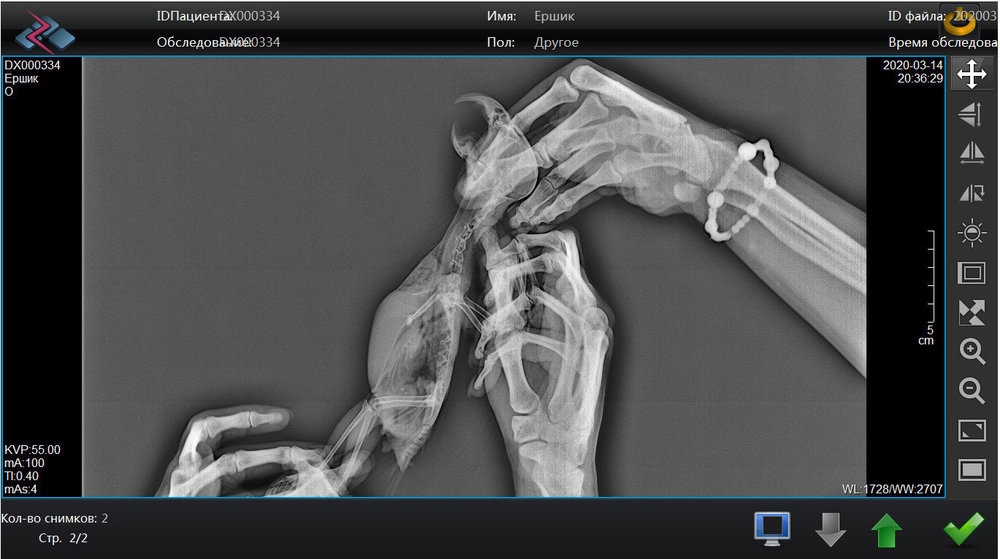

Pipka Опубликовано 25 марта, 2020 Автор #56 Опубликовано 25 марта, 2020 19.03.2020 в 19:28, Город сказал: Держитесь!! @Город , пасип! Мы держимся. 19.03.2020 в 20:21, Наташенька2 сказал: Держу за вас кулачки, все будет хорошо у вас!?? @Наташенька2 , спасипки! 20.03.2020 в 07:59, Marina-P сказал: @Pipka держитесь! Вы молодчина! @Marina-P , Спасибо! 20.03.2020 в 08:32, амазон сказал: Лучше до победного. @амазон , спасибки, я тоже так думаю. 22.03.2020 в 09:06, Лефф сказал: У моего цирковирус. Пневмония была тяжелая, правда не выясняли этиологию. Очень хорошо и быстро помогли ингаляции по 30 мин каждый вечер масла чайного дерева (аромалампа под накидкой на клетку). Противогрибковыми свойствами обладает масло орегано. Это не совет, это, возможно, повод поискать в этих направлениях. @Лефф , спасибо за помощь. Мы купили розмарин и орегано. чайного дерева я не нашла. Аромалампу я что-то боюсь. просто капала ему в обычную ингаляцию и в распылитель. мне кажется, что после ингаляций намного лучше дышит нос. Всем огромное спасибо за помощь и поддержку. У нас большой прогресс. Ёршик перестал хрипеть и хлюпать носом. Нос почти зажил, но все равно жутко чихает. И еще продолжаются движения головой с открытым ртом будто тошнит. Многие мне пишут, что так проявляет себя аспергиллез. Анализ на посев из зоба ждем со дня на день. Парень повеселел, уже не хохлится и не ершится как раньше. Я сняла видео - выложу ниже. Посмотрите если не сложно на его апчихи и на эти движения головой. Кто-то из вас скажет - мол, ничего страшного в этом нет, все попугаи так делают - типо горло прочищают. Да, я знаю, но он так делает почти постоянно. Очень очень часто. Словно бедняжке что-то мешает там. Если у кого такое было во время болезни - напишите плиз. Будем вам признательны. Еще хочу выложить здесь наши рентгены с пневмонией и результаты посевов на антибиотики и пробиотики с макрофагами. Может кому-то будет на пользу. Тоже буду благодарна если глянете - может кто разбирается. Подскажите плиз.

Pipka Опубликовано 18 апреля, 2020 Автор #73 Опубликовано 18 апреля, 2020 11.04.2020 в 21:10, Мария_К сказал: @Pipkaв надежде на хорошие новости от вас. @Мария_К , И ура!!!! Они таки хорошие!!!!!!! Люди, народ, поздравьте нас с Ёршиком!!!!!!! Мы поправились!!!! Не надо больше уколов, мерзких гадких заворачиваний в полотенце и принудительных выпаиваний горьким лекарством. МЫ ЗДОРОВЕНЬКИЕ!!!!! Посмотрите какой у нас чистенький и светленький рентгенччииккккк!!!!!!! Никаких затемнений, никаких гранулем или остаточных швов на легких. В сравнении с тем что было - день и ночь. Даже мне стало понятно и видно все. Мы поправились. По клинической картине: чихов нет, хрипов-сипов нет, нос чистейший, морду не трет, головой не дергает. Чуть позже выложу ввидео с ним. Пока вот рентген. Господи, как же я счастлива!!!!! Про липому все также. Без изменений. Но нам сказали что это фигня. Если будет правильно питаться и двигаться то больше чем есть не вырастет...

Pipka Опубликовано 18 апреля, 2020 Автор #74 Опубликовано 18 апреля, 2020 Извините, полосы - это мерцание на компе от телефона. Мне так не терпелось, что я прямо с компа на телефон щелкнула. а так ответ на диске, а у меня дома дисковода нема.